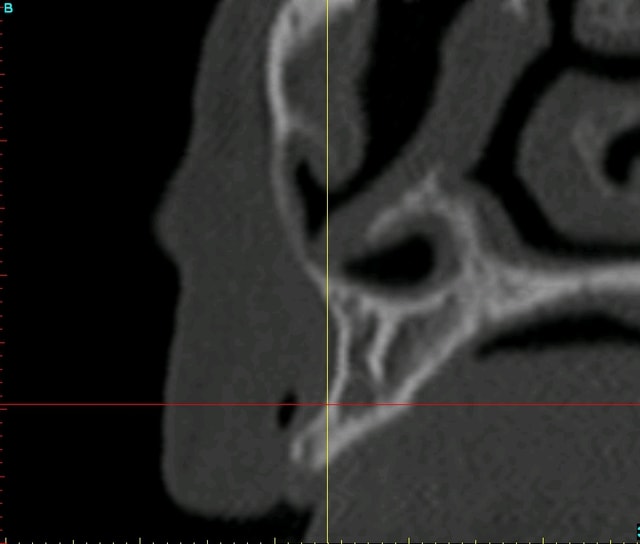

bon, pour que vous puissiez estimer l'ampleur du travail, je vous poste les coupes scan et les photos de la réplique plastique...;-)

quand on voit mes doigts sur les photos, on se rend mieux compte de la minuscule bouche de cette patiente (et je n'ai pas des mains de charretier!!!)

par ex, le moyen d'augmenter le volume osseux...pxav aurait dit "expansion"...pourquoi pas, mais c'est quand même très fin et amha avec pour résultat des implants dont l'axe aurait été très vestibulés (même si pour 13 çà aurait peut être été jouable...)...pas très simple pour la gestion de l'esthétique...

d'autres auraient dit: ROG peut être même avec pose simultanée des implants...ancrer de manière sûre les 2 implants dans si peu de nonos, je pense pas savoir faire...

donc vous l'aurez compris: greffe biobank...un seul greffon cortico spongieux (vu la petite taille de ce maxillaire) a été nécessaire, avec quand même 2 fioles de copeaux en plus...